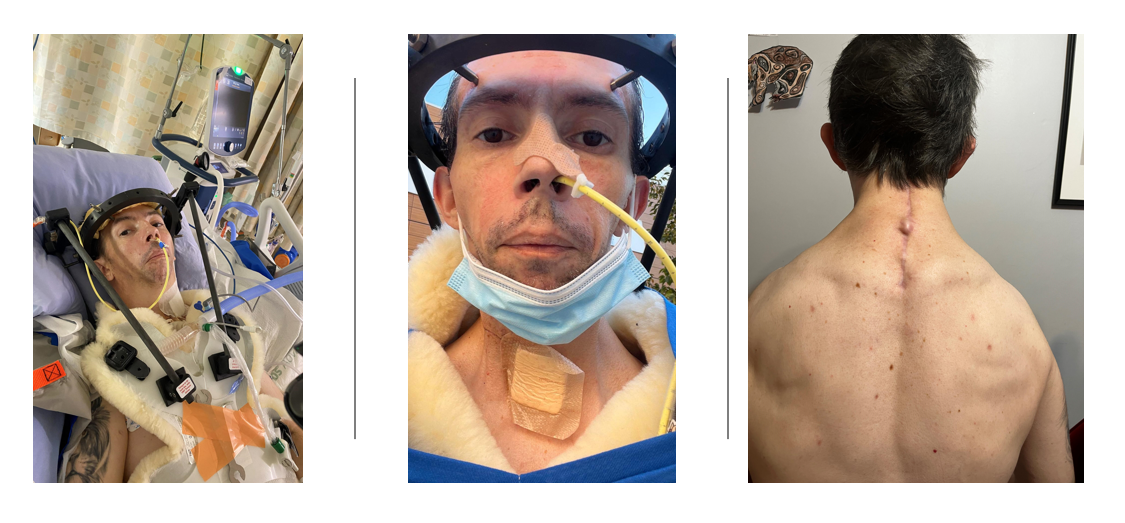

I should have known it was too good to last… a sledding accident at the end of 2021 badly worsened my neck — displacement went from 1.7 to 3.4 mm. In 2022 I had emergency cervical spinal fusion. After the operation I caught pneumonia and my weight fell from 122 pounds to 95 pounds. I am now 5 feet 10 inches tall (I lost an inch from spine compression and an inch from collapsed feet). Swallowing is very difficult. Food gets stuck, my heart rate goes above 100 bpm, and I live on soft or pureed food and shakes. My BMI is approximately 13.6 — under-nutrition.

- Chest X-ray Displaced fracture of the right 7th rib, pushed down approximately 1 cm. Narrow thoracic cavity at the top consistent with skeletal dysplasia. Extra soft-tissue calcification around both shoulders. Old T9 vertebral collapse visible. Cervical fusion hardware present. Kyphosis more pronounced.

◆ ◆ ◆HCS has taken height, weight, strength, easy eating, and parts of my daily independence. It has given me deformed bones, fractures that heal slowly or not at all, skin problems, infections, and constant pain. But it has never taken my family, my memories of work and sports, or my hope to help others who live with rare conditions.